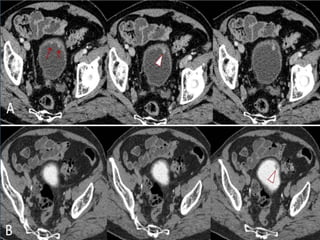

• #17 METASTASIS GANGLIONAR DE CARCINOMA UROTELIAL. A) Imagen axial de TCMD que muestra importante componente adenopático ilíaco izquierdo con centro de aspecto necrótico y periferia hipervascular afectando parcialmente hueso ilíaco homolateral (punta de flecha en A). B) Adenopatía inguinal izquierda de similares características siendo todas ellas compatibles con afectación metastásica. C) Reconstrucción multiplanar coronal. Adenopatía inguinal izquierda referida previamente (asterisco).

• #18 CARCINOMA ESCAMOSO. Imágenes axiales por TCMD en fase nefrográfica (A) y en dase excretora (B) que muestran engrosamiento mural de pared antero-lateral derecha de vejiga urinaria que se realza tras la administración de contraste y presenta crecimiento endoluminal. Se observan signos que sugieren infiltración de la grasa perivesical adyacente a la pared lateral derecha de la vejiga (punta de flecha).

• #20 RTU: Reseccion transuretral